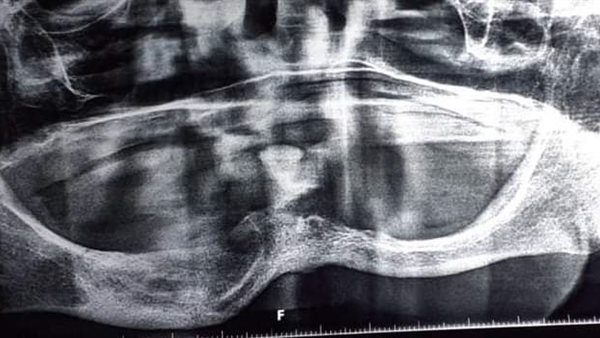

نجح فريق جراحة الفم والأسنان بوحدة الأسنان، بمستشفيات جامعة بنها برئاسة الدكتور سمير حلاوة، استشاري جراحة الفم والوجه والفكين، في استئصال كيس بالجهة اليمنى من الفك السفلي لمريضة تبلغ من العر 72 عاما ترتدي طاقم أسنان كاملا، وتعاني من أمراض مزمنة “ضغط وسكر”، وبمراجعة التاريخ المرضي للحالة ومطابقة الأشعة المقطعية والبانوراما للفك بعد سحب عينة من سائل الكيس.

وجاء التقرير المبدئي للفريق الجراحي المكون من الدكتور السيد فهم استشاري جراحة الفم والأسنان والدكتور مصطفى محمود و الدكتورة نادين طلعت والدكتورة رضوى رضا والدكتورة إيمان السيد وتحت إشراف الدكتور عمرو توفيق رئيس الوحدة، بضرورة استئصال نصف الفك السفلي وتركيب شريحة معدنية، ولكن حرصا على حالة المريضة تم عمل تسريب وقتي للكيس “marsupialization” لتقليل الضغط الداخلي وتقليص حجم الكيس لأقل حجم ممكن، وتم استخدام طقم أسنان المريضة بعمل سدادة أكريلك لفتحة التسريب لإمكانية غسل وتعقيم الفجوة من مرتين إلى ثلاث أسبوعيا بالوحدة، على مدار عام كامل من المتابعة.

وتم استئصال الكيس بعد الاطمئنان لوجود كمية كافية من عظام الفك لمنع الكسر المحتمل وتم الاستعانة بعظم صناعي لملأ الفجوة، وإعادة ضبط الطقم الأصلي ليكون داعما للجرح، وبعد متابعة ستة أشهر كانت النتيجة المذهلة بتكون عظم جديد للفك واختفاء أثر الكيس وعودة حجم الفك إلى صورته الأصلية مع استخدام نفس طقم الأسنان الخاص بالمريضة في الطعام.